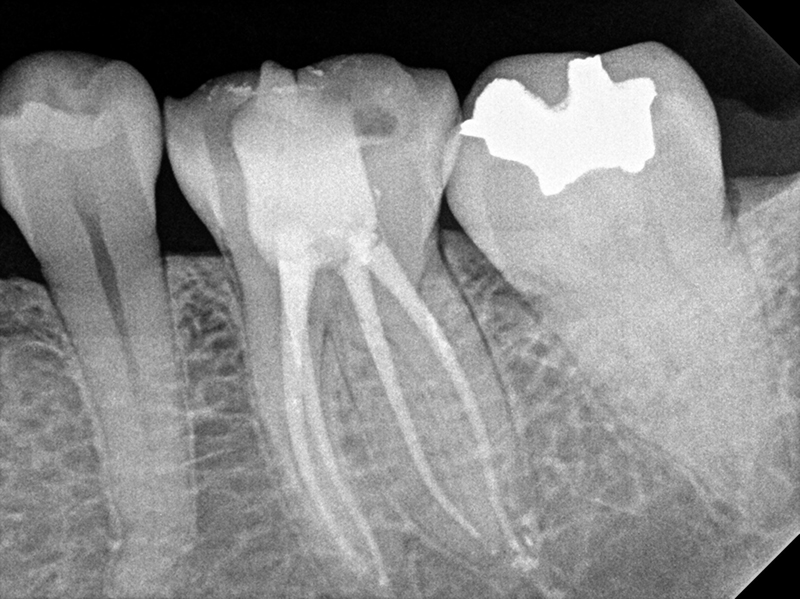

재신경치료

신경치료를 했는데도 염증이 재발하는 경우, 치아 상태에 따라 재신경치료가 가능합니다.

재신경치료는 기존에 신경치료로 충전한 재료를 모두 제거하고 신경치료를 다시 하는 술식으로,

신경치료에 비해 난이도가 높지만 치아를 보존할 수 있는 중요한 술식입니다.